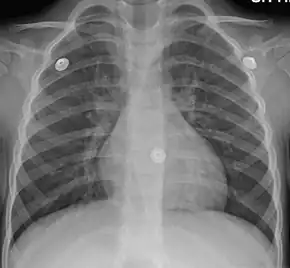

In more than 90% of cases, the cause is a viral infection.[1] These viruses may be spread through the air when people cough or by direct contact.[2] Risk factors include exposure to tobacco smoke, dust, and other air pollution.[2] A small number of cases are due to high levels of air pollution or bacteria such as Mycoplasma pneumoniae or Bordetella pertussis.[1][9] Diagnosis is typically based on a person's signs and symptom.[4] The color of the sputum does not indicate if the infection is viral or bacterial.[1] Determining the underlying organism is typically not needed.[1] Other causes of similar symptoms include asthma, pneumonia, bronchiolitis, bronchiectasis, and COPD.[1][7] A chest X-ray may be useful to detect pneumonia.[1]

- A chest X-ray is useful to exclude pneumonia which is more common in those with a fever, fast heart rate, fast respiratory rate, or who are old.[7]